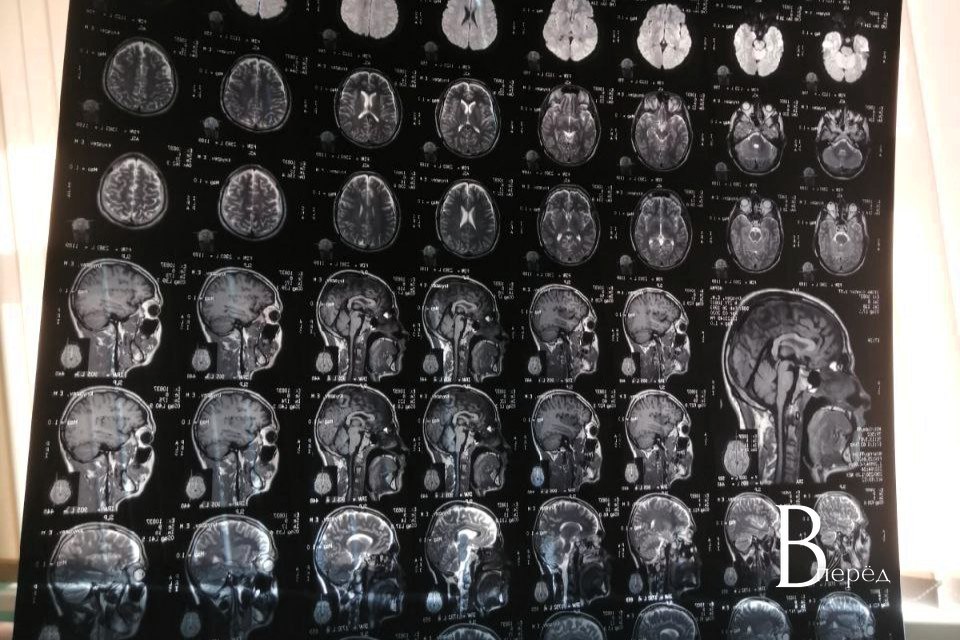

Почему бокал вина делает беседу приятнее, а несколько бокалов могут привести к вспышке гнева или глубокой тоске? Как эпизодическое употребление перерастает в навязчивую потребность, которая перестраивает работу нейронных сетей? В поисках ответов мы обратимся к нейробиологии — и узнаем, что происходит под черепной коробкой, когда в кровь поступает этанол, и к каким долгосрочным последствиям для эмоций и поведения это может вести. Из источника «Тульские известия»